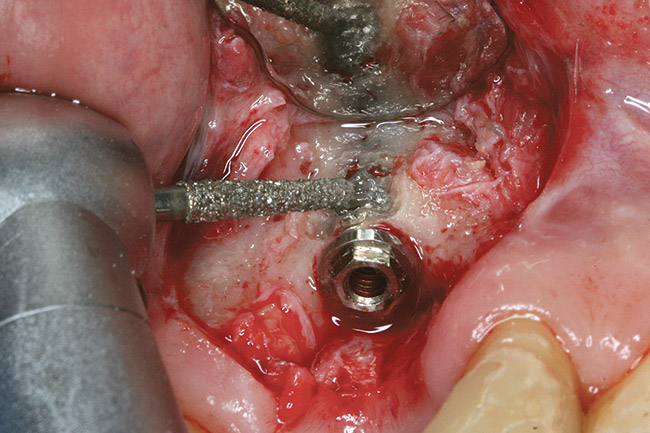

Figure 8  Trephine bur used to remove bone around the implant.

Figure 8

Figure 12  Trephine bur used to remove bone around the failed implant guided by the implant mount.

Figure 12